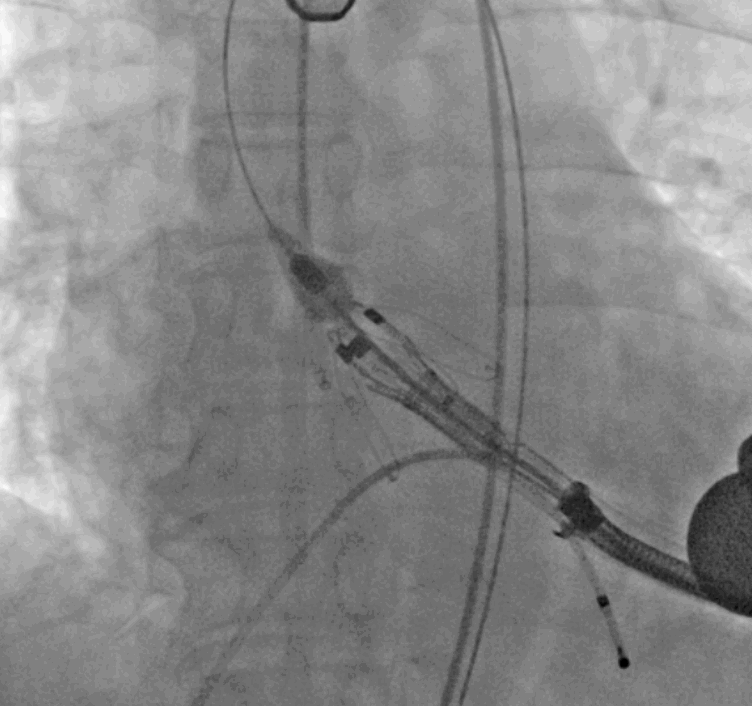

术中瓣膜释放过程